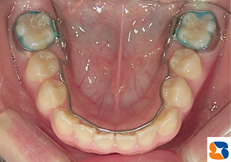

コラム「下の歯並びを広げる装置」の画像